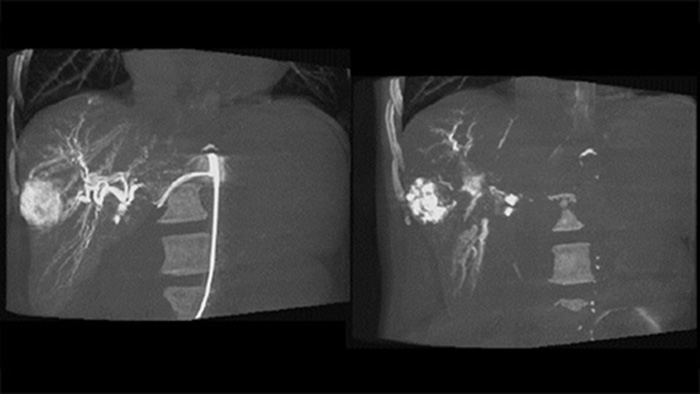

Uma aquisição 3D pós-embolização permite que você visualize a deposição direcionada no tumor do material embólico, como Lipiodol ou microesferas radiopacas.5

O Dual View permite a visualização simultânea da imagem 3D da fase arterial pré-embolização e da imagem pós-embolização para avaliar o desfecho do tratamento.